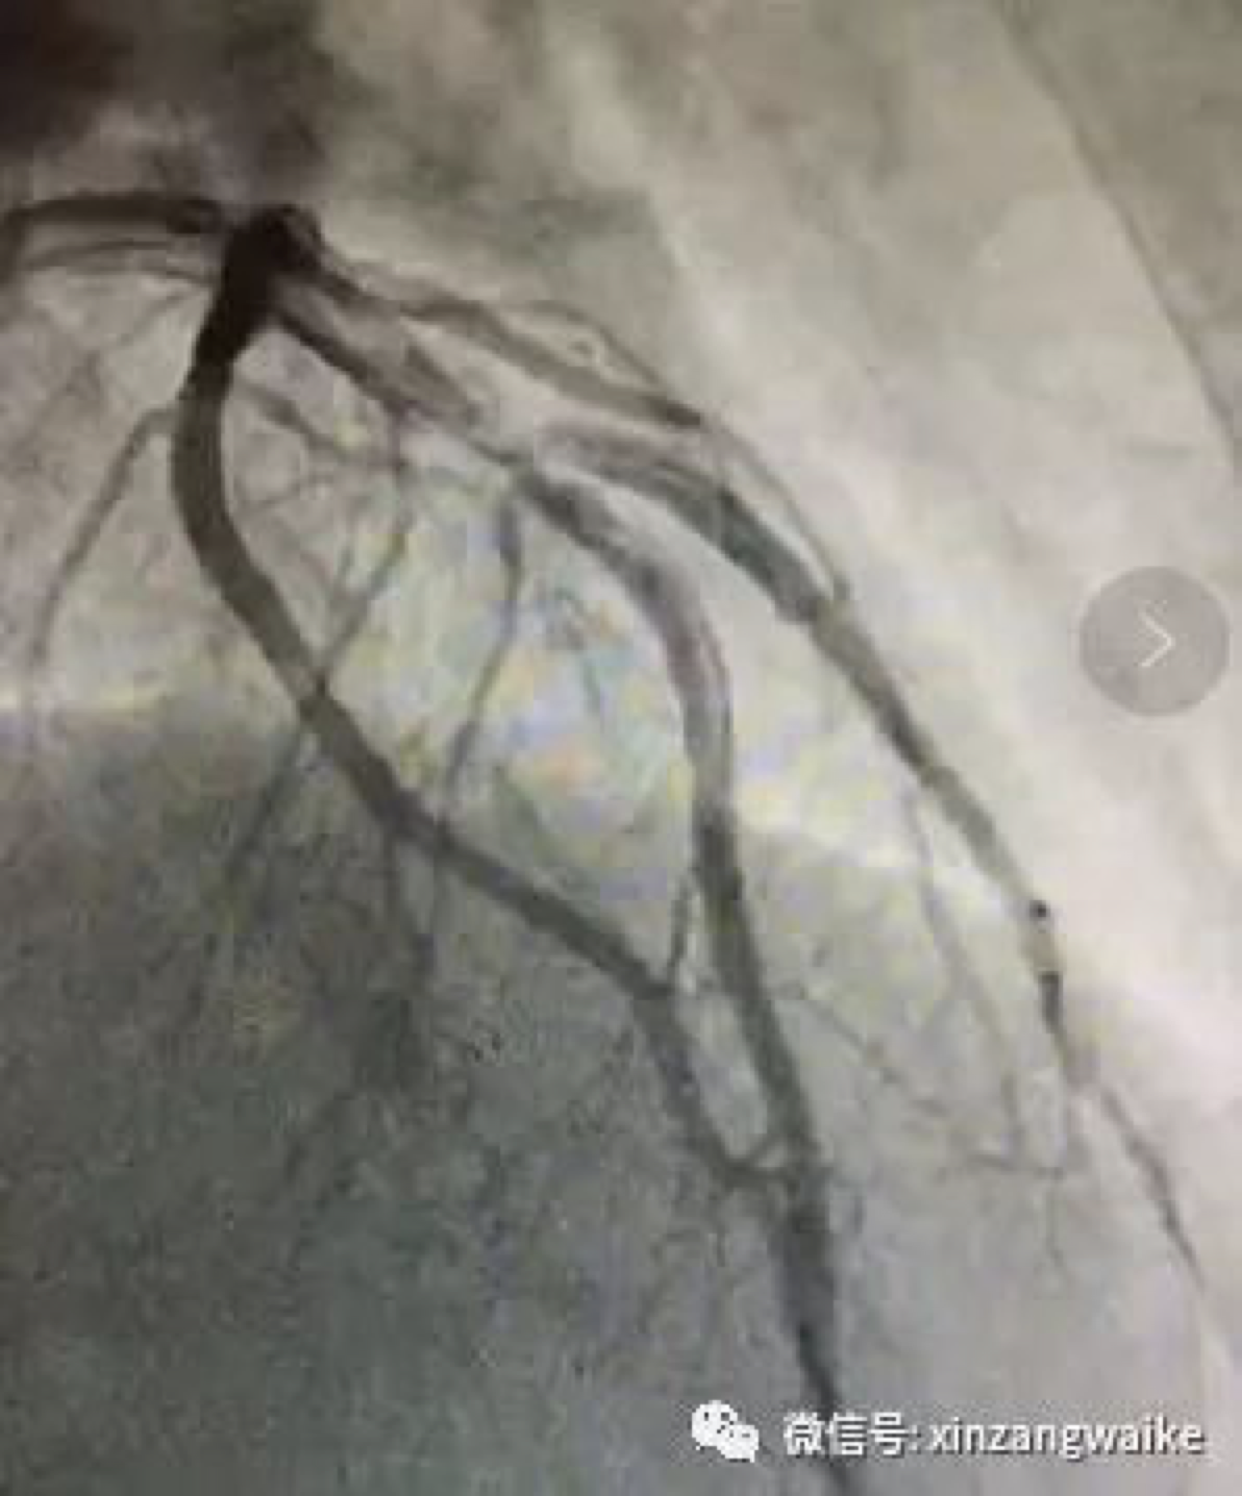

(如上图所示:冠状动脉前降支及第一对角支分叉处95%狭窄,一旦堵塞,死亡率极高)